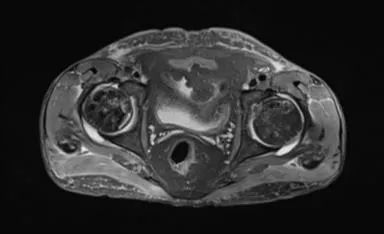

双侧股骨头前上面有大面积的骨髓异常,T1为低信号,在T1和T2W图像上,周围环绕着低强度的边缘。双股骨头呈线性软骨下骨折/断裂,在脂肪抑制图像上得到很好的评价。两侧均有轻度塌陷/扁平的轻微轮廓畸形。这些发现代表了双侧股骨头缺血性坏死。

盆腔内存在小体积游离液。弥漫性软组织水肿见于前腹壁及骨盆、大腿。这些发现是由于慢性肾脏疾病造成的。